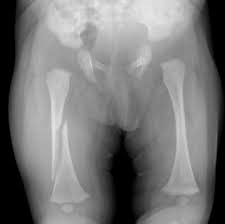

- Uzun kemik kırıkları: Alışılmış oyun aktivitesinde, futbol, basketbol gibi karşılaşma sporlarında büyük çocuklarda bazı tür bağ zedelenmeleri ve küçük kırıklar oluşabilmektedir. Öyküyle uyumlu olduğunda bunlar Çİ bulgusu değildir. Ancak transvers veya spiral femur (uyluk) fraktürü gibi bazı türler kesinlikle oyun aktivitesi ile bağdaşmaz ve Çİ bulgusudur (Şekil 1).

Şekil 1. Spiral femur (uyluk) fraktürü.